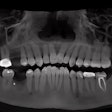

Clinical tip: How to increase case acceptance using CBCT

Clinical tip: Alignment of teeth and attachment loss